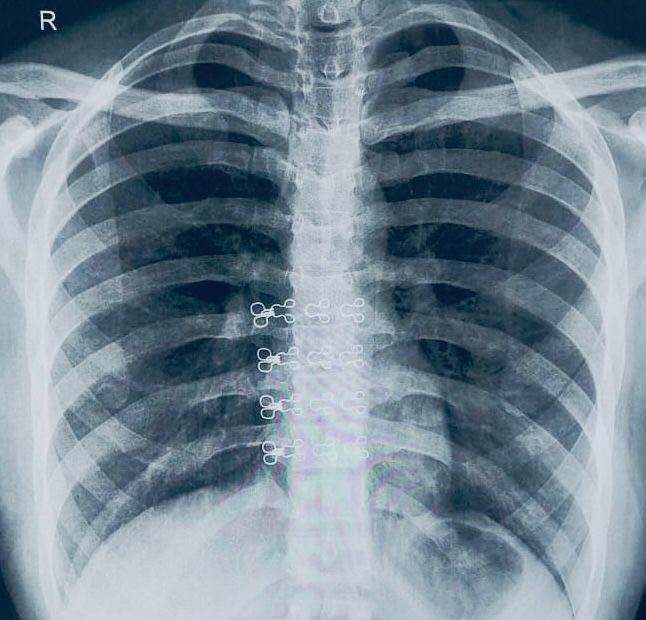

وعلى الفور، قام الفريق الطبي بإجراء الفحوصات والإجراءات اللازمة، والتي كشفت عن استقرار المقذوف الناري داخل أنسجة الرئة اليمنى ليتم التنسيق مع مستشفى القلب الجامعي، ويتم تشكيل فريق طبي تحت إشراف الأستاذ الدكتور محمد عياد، وبرئاسة الدكتور محمد فاروق عبد الحافظ، مدرس جراحة القلب والصدر، وضم كلا من، الطبيب علي زين، مدرس مساعد بالقسم، والطبيب محمد ببلاوي، والطبيب مروان أحمد، أطباء مقيمين بالقسم، يعاونه فريق طبي من قسم التخدير والرعاية المركزة تحت إشراف الأستاذة الدكتورة هالة سعد رئيس القسم، وضم كلا من الدكتور عبد الرحمن حمدي، مدرس التخدير والرعاية المركزة، والطبيب أحمد وهبه مدرس مساعد بالقسم، بينما ضم الطاقم التمريض الجراحي المتميز كل من، أخصائي تمريض كيرلس جمال، وفني تمريض خالد مصطفى، وفني تمريض هند عبد المنعم.

وتمت مناظرة دقيقة للحالة وإجراء الأشعات اللازمة التي أكدت استقرار المقذوف بين أغشية الرئة، ليقوم الفريق الطبي بإجراء جراحة دقيقة للغاية، وتم استخراج المقذوف الناري بنجاح باستخدام منظار الصدر الجراحي من خلال فتحة جراحية لا تتعدى 2 سم، مما ساهم في الحفاظ على سلامة الرئة وتقليل التلف إلى أدنى حد، بالإضافة إلى الحفاظ على الشكل الجمالي لجدار الصدر.